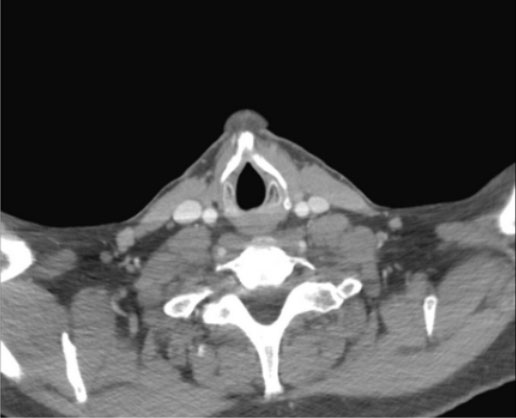

A 46-year-old male with a past medical history of hypothyroidism and cannabis use disorder presented to his primary care physician with a globus sensation and left cervical lymphadenopathy for two weeks. A computed tomography (CT) scan of the neck with contrast identified three high attenuation areas: the first in the midline floor of the mouth extending posteriorly to the base of the tongue (1.5 × 2.2 cm) (Figure 1), the second at the base of the tongue (1.4 × 1.8 × 3.0 cm) (Figure 2), and the third in the midline of the neck just beneath the hyoid bone (1.3 cm) (Figure 3). Thyroid tissue was not identified in the orthotopic location (Figure 4). A follow-up thyroid uptake and scan confirmed that each of these high attenuation areas was also iodine avid, consistent with thyroid tissue (Figure 5). Notably, there was no uptake in the normal orthotopic thyroid location.

Figure 4: Lack of thyroid tissue at the normal orthotopic location.